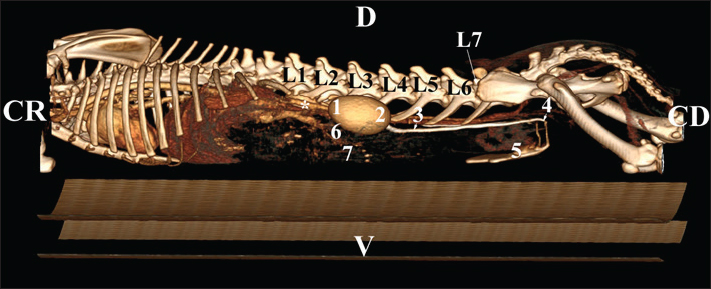

Fig. 21. Retrospective reconstruction of computed tomography data in Bones and Skin 3 mode in a rabbit. (1) XIII h rib; (2) extremitas cranialis; (3) extremitas caudalis; (4) capsula adiposa; (5) pelvis renalis (right kidney); (6) right ureter (pars abdominalis); (7) pars descendens of the duodenum; (8) pelvis renalis (left kidney); (9) left ureter (pars abdominalis); (10) lobus caudatus (proc. caudatus); (11) pars ascendens of the duodenum. Retrospective reconstruction in the Angio–Right and Left mode (right and left sides) yielded information about the localization of both kidneys in the RA. The right kidney was located in the region abdominis cranialis and region abdominis media, between Th13 (L1) and L2–L3, whereas the left kidney was located between L2 (L3) and L4 (L5) (Figs. 22 and 23).

Fig. 23. Retrospective reconstruction of computed tomography data in Angio–Right and Left 1 mode in a rabbit (left side). (1) Extremitas cranialis; (2) Extremitas caudalis; (3) Left ureter (pars abdominalis); (4) Left ureter (pars pelvina); (5) Vesica urinaria; (6) Cecum; (7) Colon ascendens; (*) Aorta abdominalis. Statistical and metric analysesSoft tissue density was measured on pre-contrast CT scans to obtain objective data. The density of the right kidney was 40.28 ± 6.6 HU, and that of the left kidney was 43.36 ± 5.2 HU (Table 1). Table 1. CT values of rabbit kidneys in the HU.